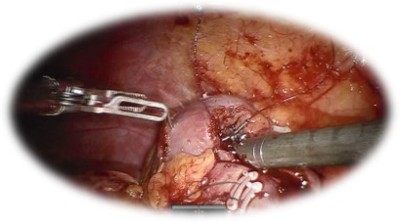

Nefrectomia radicală robotică:

• Presupune îndepărtarea rinichiului afectat tumoral împreună cu fascia Gerota în bloc și a ganglionilor limfatici regionali

• Este indicată în cazul tumorilor voluminoase renale

• Oferă:

• Spitalizare scurtă, cu recuperare rapidă

• Sângerare redusă

• Risc scăzut de complicații intra/ postoperatorii